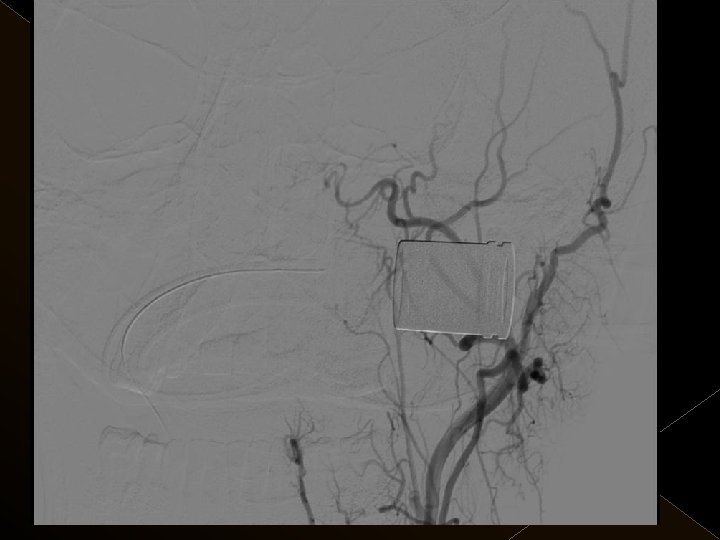

� İnme tedavisinde iv tpa uygulamasını takiben � intraarteriyel (İA) trombolitik tedavi (ia tpa ve ia mekanik trombolizis) � İA stent yardımı ile trombektomi yöntemleri kullanılarak tedaviye cevap ve komplikasyonlar araştırıldı.

KOMPLİKASYONLAR Ponksiyon bölgesi komplikasyonları � Trombektomi stentine ait komplikasyon (*1) � Diseksiyon(*2) � Karotikokavernöz fistül (‘ 1) � Hemorajik komplikasyonlar(‘ 5) Semptomatik-nonsemptomatik � İskemik komplikasyonlar (3) � Reoklüzyon (2 i. a) � Kontrast madde nefropatisi �

Acil servise başvuru süreleri: 1 -4. 5 saat Başvuru sırasındaki ortalama NIHSS skoru: 23 25 hastanın 21’inda kontrol serebral anjiografide tıkanıklığın tamamen açılmış olduğu görüldü. � Baziler arter ve ICA tıkanıklığı olan 4 hasta kaybedildi. � 19 hastanın 16’sında NIHSS skorlarında işlem sonrasında 24. saatte yapılan klinik değerlendirmede ortalama 10 puanlık düşüş saptandı. � � �